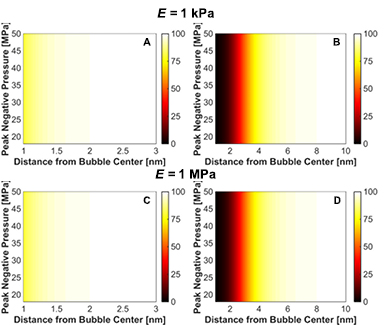

Standard image High-resolution imageChanges in cell viability induced by strain from the bubble collapse are shown in figure 12. While strain during the expansion pushes red blood cells away from the bubble, strain during collapse pulls the red blood cells toward the bubble. For conditions of massive bubble expansion (i.e. medium elasticity less than 20 MPa), the cell viability at a fixed distance from the bubble varied by less than 0.1% over the range of media elasticity or insonation conditions considered in this study. Bubble collapse-induced changes in cell viability appear to be restricted within 2 nm for microtripsy excitations, and 10 nm for shock scattering histotripsy.

Figure 12. Change in cell viability, expressed in terms of percent in the colorbar, due to strain at minimum bubble radius for microtripsy insonation (left column) and shock-scattering histotripsy insonation (right column) for medium elastic modulus of 1 kPa (panels (A) and (B)) and 1 MPa (panels (C) and (D)). The fundamental frequency of the insonation was 1 MHz for both calculations, and the initial bubble diameter was 5 nm for the microtripsy excitation and 20 nm for the shock scattering histotripsy excitation.

Download figure:

Red blood cell viability surrounding histotripsy cavitation activity was modeled based on measurements of impulsive stretching of erythrocytes (Li et al 2013). Strain fields surrounding the bubble were rapidly attenuated within 50 µm from the bubble wall, consistent with previous calculations of histotripsy-induced cavitation (Mancia et al 2017). Only red blood cells within a few micrometers from the bubble wall experienced lethal strain (table 3), and the erythrocyte viability increased sigmoidally with distance away from the bubble. On a macroscopic level, the limited distance over which red blood cell viability is reduced observed in this study is consistent with the sharp boundaries observed in histotripsy lesions (Parsons et al 2006, Kieran et al 2007, Vlaisavljevich et al 2013a, Darnell et al 2015). In vitro studies have demonstrated histotripsy-induced breast cancer cell bisection occur only within a few micrometers to a nucleated bubble (Vlaisavljevich et al 2016). Under the similar insonation conditions, the calculations in this study indicate changes in red blood cell viability would be restricted within 1 µm of the bubble (figures 11(C) and (E)).